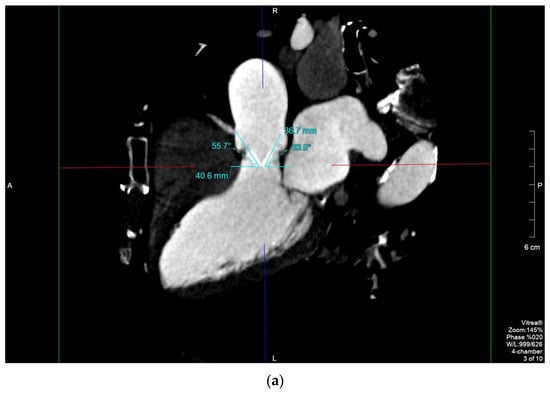

Female, 83 years old (y/o), with hypertension, hypercholesterolemia, carotid vasculopathy (type III, AHA) and history of (h/o) smoking affected by degenerative aortic stenosis, underwent valvular replacement with a St. Jude 21 mm mechanical prosthesis in 2000. Twenty years later, she was hospitalized for respiratory distress. TTE showed left ventricle (LV) dysfunction with severe prosthetic valve stenosis (aortic acceleration time (AAT): 140 ms, transaortic maximum speed: 4.8 m/s, maximum/median gradient: 90/52 mm Hg, indexed effective orifice area (EOA): 0.3 cm2/mq, EF: 35%). TEE showed hypomobility of the anterior leaflet. Due to the shielding from the prosthesis, it was unclear if there was a thrombus or a pannus (Supplementary Video S1). As it is possible to differentiate between a pannus and a thrombus due to their different radiological density (HU > 145 and > 90, respectively) [9], MDCT was performed, and it showed that the anterior aortic leaflet was stuck and surrounded by hypodense tissue (Hounsfield units (HU): 203.8) interposed between native and prosthetic annuli (effective orifice area (EOA): 45 mm2, EOA/0.15) indicating a pannus (Figure 1a–c). This information was of utmost importance as instead of staring anticoagulant treatment, the patient directly underwent repeat surgical repair with a bioprosthesis. The diagnosis of pannus was confirmed by pathology.

Figure 1.

MPR of a St. Jude PHV (10% of the RR interval): long-axis view showing the maximum opening angle of the anterior and posterior leaflets, 55.7° and 63.9° (normal range, 75–90°), respectively (a); region of interest (ROI) on the periprosthetic hypodense tissue (b); 3D anatomical model of the PHV involved by the pannus (c).

The distinction between a pannus and a thrombus may be challenging [3,12]. It has been shown by recent studies that MDCT is a very sensitive technique capable of differentiating a pannus from a thrombus by detecting its exact location and measuring its attenuation [14,15]. A pannus usually affects the ventricular side of the PHV and has attenuation similar to myocardium [12]; on the contrary, a valvular thrombus usually has lower attenuation and preferentially involves the aortic side of the prosthesis [12]. In case 1, attenuation of the hypodense perivalvular tissue was 50 Hounsfield units (HU), the LV wall [16]. Moreover, with the high spatial resolution of MDCT, it is possible to perform accurate calculations of the leaflet’s opening angles (Figure 1c), the maximum pannus width and the pannus encroachment ratio, all of which are associated with the magnitude of PHV dysfunction [17].